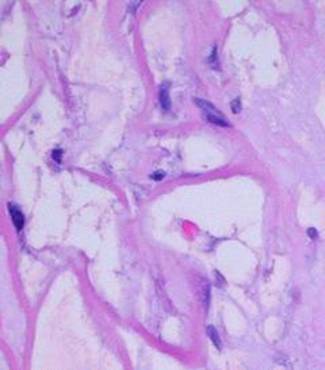

Figure 2

This micrograph, 17 days after placement, shows the sizes and relationships of cells and matrix.  The smallest dark round lymphoid cells are the pioneer cells, the larger flatter ones are the transitional cells.